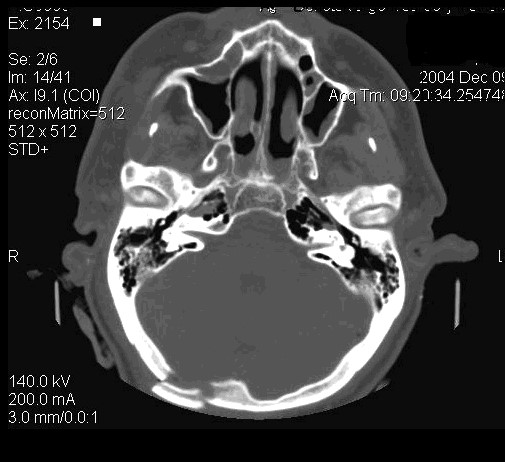

Компьютерные томограммы головы производят при горизонтальном положении пациента, выделяя изображения отдельных слоев черепа и головного мозга (рис. 34).

Рис. 34.         КТ изображение  головы в аксиальной плоскости. Определяется перелом затылочной кости на уровне внутреннего затылочного выступа справа.

Специальной подготовки к исследованию не требуется. Полное исследование головы состоит из 12--17 срезов (в зависи­мости от толщины выделяемого слоя). Об уровне среза можно судить по конфигурации желудочков мозга; они, как правило, видны на томограммах. Часто при КТ мозга используют методику усиления путем внутривенного введения водорастворимого контрастного вещества.

На компьютерных и магнитно-резонансных томограммах хорошо разли­чимы полушария большого мозга, мозговой ствол и мозжечок. Можно дифференцировать серое и белое вещество, очертания извилин и бо­розд, тени крупных сосудов, ликворные пространства. Как КТ, так и МРТ наряду с послойным изображением могут реконструировать трех­мерное отображение и анатомическую ориентацию во всех структурах черепа и головного мозга. Компьютерная обработка позволяет полу­чить увеличенное изображение интересующей врача области.

При изучении структур мозги МРТ имеет некоторые преимущества перед КТВо-первых, на MP-томограммах более четко различаются структурные элементы головного мозга, отчетливее дифференцируются белое и серое вещество, все стволовые структуры. На качестве магнитно-резонансных то­мограмм не отражается экранирующее действие костей черепа, ухудшаю­щее качество изображения при КТ. Во-вторых, МРТ можно производить в разных проекциях и получать не только аксиальные, как при КТ, но и фронтальные, сагиттальные и косые слои. В-третьих, это исследование не связано с лучевой нагрузкой. Особым достоинством МРТ является возмож­ность отображения сосудов, в частности сосудов шеи и основания головно­го мозга, а при контрастировании гадолинием -- и мелких сосудистых вет­вей (см. рис. 35 и 36).